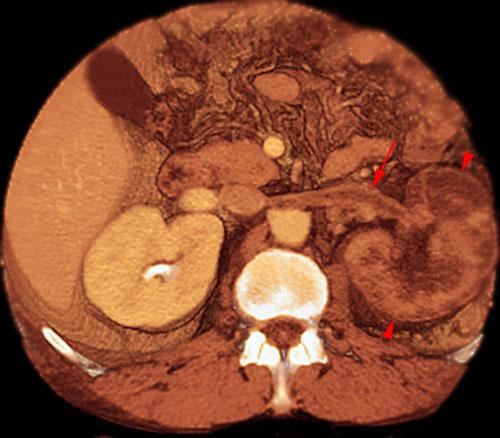

La patología venosa de las venas renales bien de origen compresivo o por trombosis, precisa de un estudio ecográfico morfológico o con técnica Doppler.

El diagnóstico se realiza habitualmente mediante AngioTC en fases arterial y venosa que permitirá comprobar la permeabilidad o compresión de la misma y su causa.